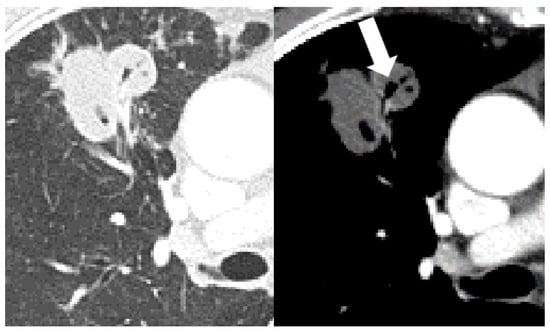

| Bronchial erosion | 157 (47) | 110 (44) | 9 (30) | 38 (73) | <0.001 | 0.157 | <0.001 | <0.001 |

| Cavitation | 157 (47) | 109 (43) | 7 (23) | 41 (79) | <0.001 | 0.038 | <0.001 | <0.001 |